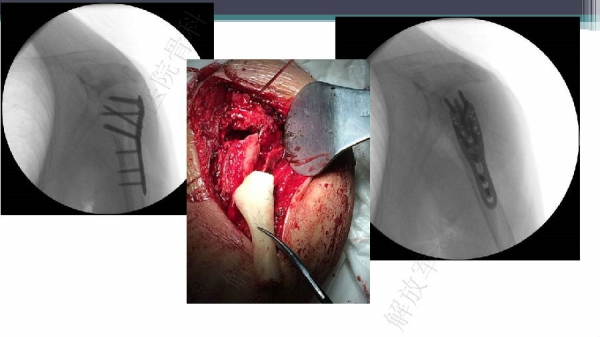

导 语:肱骨近端骨折仍是最常见的骨科损伤之一,尤其好发于老年人群。移位型肱骨近端骨折通常需要手术治疗,但是由于骨折粉碎、骨质较差,手术治疗往往会比较困难。随着锁定钢板的发明,使得并发症显著降低。但仍存在一些问题,对于内侧皮质不连续缺乏内侧可靠支撑,合并老年骨质疏松的病人,锁定钢板吊臂样结构就无法满足力学要求,随着康复锻炼可能出现断板、断钉、螺钉切出肱骨头等并发症。本期解放军总医院骨科专家们对老年肱骨近端骨折的问题与创新手术技术进行了详细讲解。